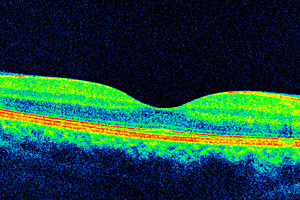

Detaillierte Querschnittsanalyse der Gewebestruktur der Netzhaut

Beispiel OCT-Scan

Querschnittsanalyse der Netzhautschichten

Die optische Kohärenztomographie (OCT) dient der schichtweisen Untersuchung des Augenhintergrundes. So können folgenschwere Netzhauterkrankungen frühzeitig erkannt werden. Dieses Verfahren nimmt eine Querschnittsanalyse der Gewebestruktur der Netzhaut vor und ähnelt damit einer Ultraschall-Untersuchung – nur ist es schneller und liefert eine etwa 40-fach höhere Bildauflösung. So können auch Feinheiten klar differenziert werden.

Dadurch dass die Netzhaut nicht nur oberflächlich, sondern auch in Schichten abgebildet wird, erlangt der Augenarzt tiefere Kenntnisse über die Beschaffenheit der Netzhaut und der Aderhaut. So kann die optische Kohärenztomographie oft auch aufwändige fluoreszenzangiografische Untersuchungen ersetzen, bei denen zunächst Farbstoffe injiziert werden müssen, um eine Abbildung unterschiedlicher Schichten zu ermöglichen.